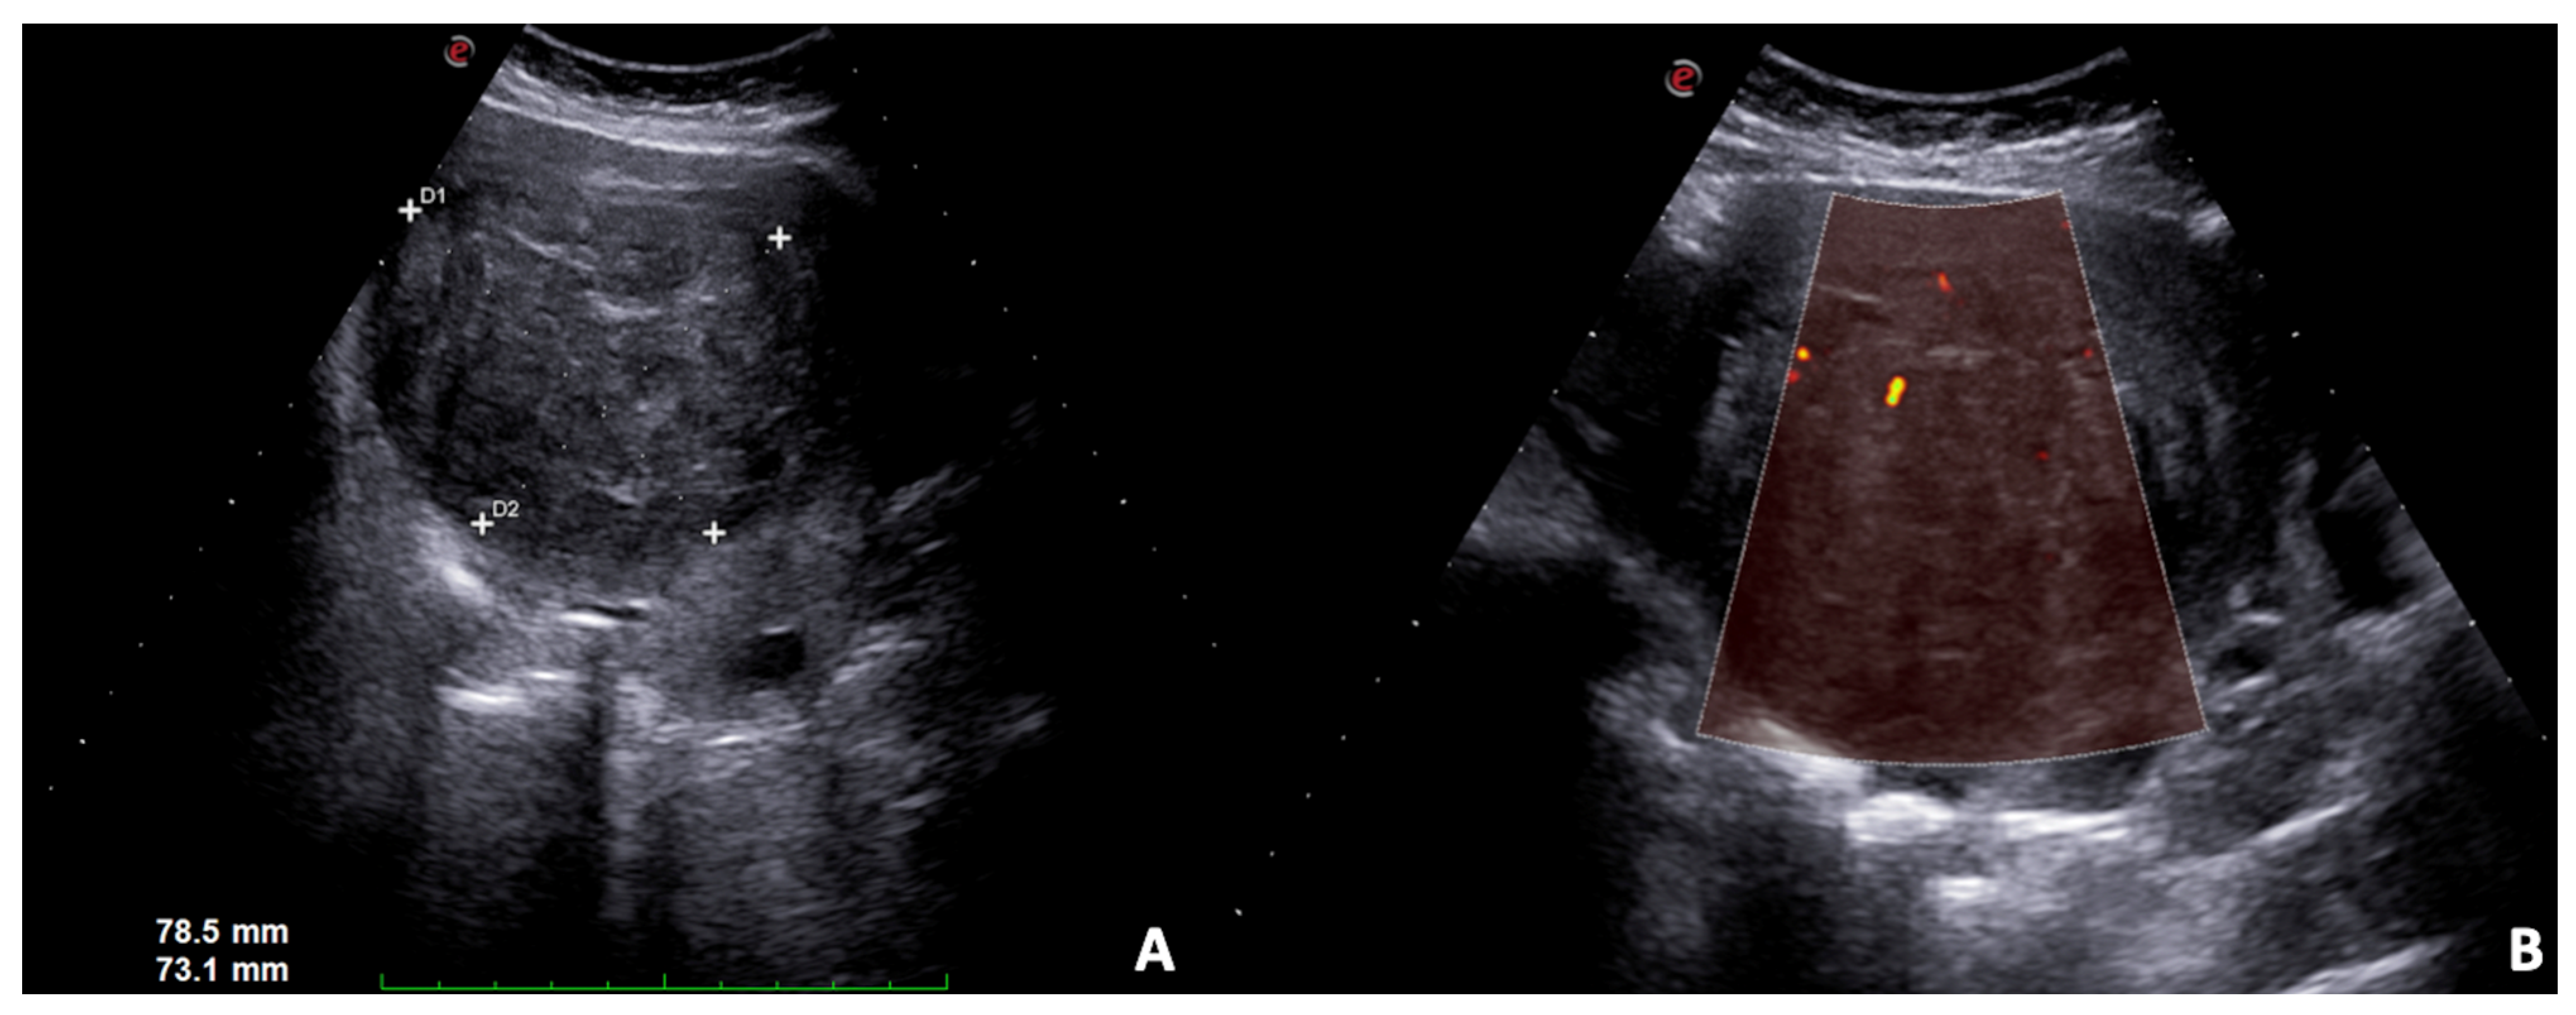

3.3. Uterine Leiomyoma

- Woźniak, A.; Woźniak, S. Ultrasonography of uterine leiomyomas. Menopausal Rev. 2017, 16, 113–117. [Google Scholar] [CrossRef] [PubMed]

- Chill, H.H.; Karavani, G.; Rachmani, T.; Dior, U.; Tadmor, O.; Shushan, A. Growth pattern of uterine leiomyoma along pregnancy. BMC Women’s Health 2019, 19, 100. [Google Scholar] [CrossRef] [Green Version]

- Wilde, S.; Scott-Barrett, S. Radiological appearances of uterine fibroids. Indian J. Radiol. Imaging 2009, 19, 222–231. [Google Scholar] [CrossRef]